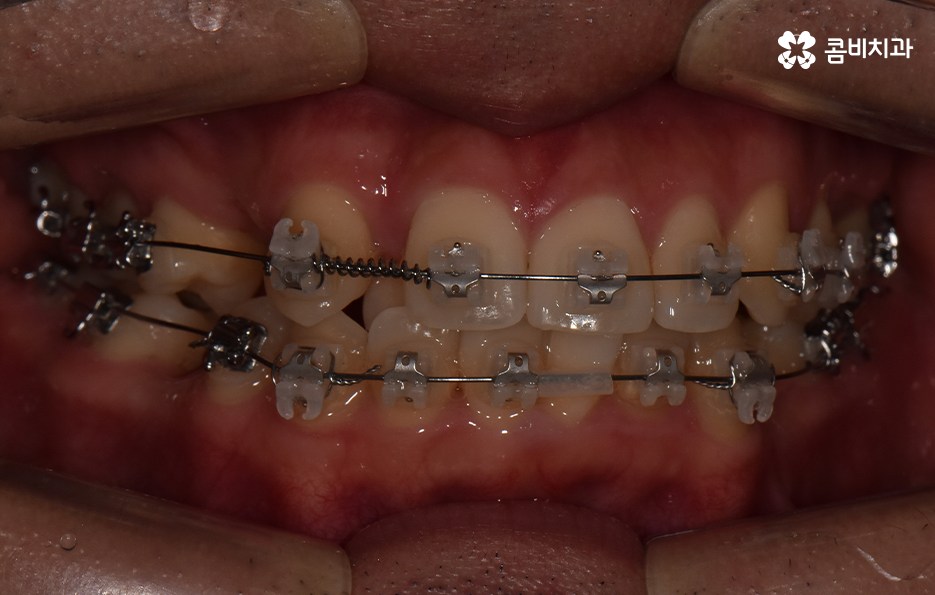

요즘은 앞니만 약간 벌어져도 교정을 하는 분들이 크게 늘고 있기 때문에 덧니가 심하지 않아도 교정을 하는 분들도 많기 때문에 덧니 교정 사례에서도 비발치 사례도 많지만 보편적으로 덧니 발치교정 사례가 많은 것도 사실이기 때문에 어떠한 경우에는 발치교정이 필요하며 또한 어떻게 치아교정 계획을 세우는 것이 좋을지 오늘 포스팅에서 알아볼 거예요

다만 덧니 교정 사례에서 발치교정 사례가 많은 이유는 턱뼈가 좁아서 치아가 덧니로 자란 경우가 많기 때문에 치열을 재배열하기 위해서는 치아가 움직일 수 있는 충분한 이동공간이 필요하기 때문에 공간 확보의 목적으로서 작은 어금니 양옆, 위아래 4개를 발치를 하는 발치교정법이 보편적으로 많이 활용되고 있으며 치아의 이동 공간을 확보하는 방법으로는 발치 교정법 외에도 악궁확장, 어금니 후방이동, 치간삭제와 같은 비발치적인 방법도 가능하기 때문에 치아를 얼마나 이동시켜야 할지에 따라서 치료법은 개인차가 발생되고 있어요

덧니 교정 사례를 살펴보면 치열을 가지런하게 재배열 하는 기준만으로 보면 비발치로도 충분히 교정이 가능한 경우도 많지만 돌출입의 개선이나 입술라인 등을 고려해서 발치교정을 하게 되는 사례도 많이 있어요

치아교정의 결과에 있어서 단지 정면에서 바라보는 치열이 가지런하게 보이는 것이 아니라 얼굴형과 잘어울리는 조화로운 결과 또한 무척이나 중요하기 때문에 치아교정 후의 얼굴변화를 잘 예측하는 것이 발치교정을 판단하는데 중요한 판단 기준이 될 수 있는데요